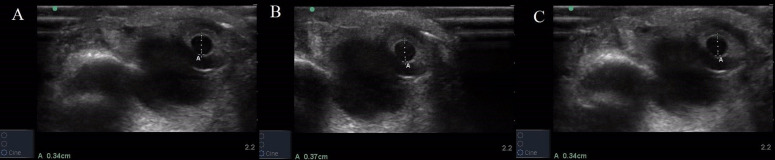

背景:早期的研究已经证明恶化的格拉斯哥昏迷评分(GCS)是颅内压(ICP)升高的标志。低GCS与瞳孔参数异常有关。目前,许多研究已经证明,超声提供了一种可行的、客观的瞳孔光反射评估方法。然而,缺乏评价客观瞳孔参数的文献,以预测患者的GCS点超声(POCUS)。材料和方法:在这项前瞻性横断面研究中,在急诊科招募了200名患者。纳入标准为18岁以上急性表现为精神状态改变的患者。排除标准是有部分球破裂或痴呆的患者。患者在休息和光刺激后接受b模式pocus引导的评估。采用Spearman’s Rank相关系数、Kruskal-Wallis群体等秩检验和受者工作特征下面积对瞳孔评价参数与GCS之间的关系进行统计分析。结果:共纳入200例患者,其中女性42例,男性158例,平均(±标准差)年龄为43.56±16.50岁,GCS为5.54±3.00岁。无反应小学生GCS评分以3 ~ 8分为主(74例,97.37%)。瞳孔直径(PD)和PD变异与瞳孔对光刺激和GCS的反应性具有统计学意义上的一致性,PD的Spearman相关系数为0.28 ~ 0.33,GCS bbbb8的Spearman相关系数为-0.55 ~ -0.50 (p值为19.68%,灵敏度为86.96% (95% CI: 82.04 ~ 91.88%),特异性为64.97% (95% CI: 58.00 ~ 71.94%)。结论:POCUS测量的PD变异和PDVR与GCS bbbb8有显著相关性。本研究显示PDVR对光刺激检测GCS >8具有良好的敏感性和较低的特异性。

Background: Earlier studies have proved deteriorating Glasgow Coma Scale (GCS) as a marker of raised intracranial pressure (ICP). Low GCS is associated with abnormal pupillary parameters. Currently, many studies have proved that ultrasound provides a feasible and objective assessment of pupillary light reflex. However, literature is lacking to evaluate objective pupillary parameters to predict GCS of the patients by point of care ultrasound (POCUS). Materials and methods: In this prospective, cross-sectional study, 200 patients were recruited in the emergency department. The inclusion criteria were patients older than 18 years with acute presentation of altered mental status. Exclusion criteria were patients who had partial globe rupture or dementia. The patients underwent a B-mode POCUS-guided evaluation at rest and after light stimulation. Statistical analysis of relationship between pupillary assessment parameters and GCS was performed using Spearman's Rank correlation coefficient, Kruskal-Wallis equality-of-populations rank test, and area under the receiver operating characteristic. Results: The study consisted of 200 (42 female, 158 male) patients with mean (± standard deviation) of age and GCS of 43.56 ± 16.50 years and 5.54 ± 3.00, respectively. Majority of non-reactive pupils had a GCS Score of 3-8 (74 cases, 97.37%). The Pupillary diameter (PD) and PD variation showed statistically significant agreement with pupil reactivity to light stimulation and GCS, with Spearman's correlation coefficient ranging from 0.28 to 0.33 for PD, and -0.55 to -0.50 (p-value <0.05) for PD variation, respectively. PD variation rate (PDVR) is the percentage change in the magnitude of constriction of PD on light stimulation. PDVR of >19.68% had a sensitivity of 86.96% (95% CI: 82.04 - 91.88%) and specificity of 64.97% (95% CI: 58.00 - 71.94%) to detect GCS>8. Conclusion: PD variation and PDVR measured by POCUS has significant correlation with GCS >8. The study showed good sensitivity and low specificity of PDVR on light stimulation to detect GCS >8.